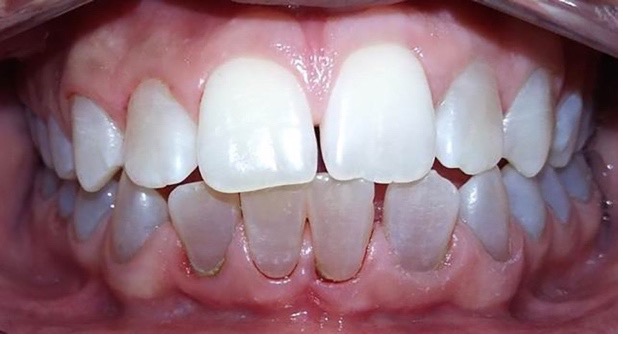

Figura 11: Controles clínicos 2018

En el último control realizado en el año 2018 (Figura 11) el paciente mantuvo el estado de salud logrado. El análisis cariogénico fue moderado (por su historia pasada de caries y su condición biológica específica) y el gingivoperiodontal bajo. El paciente continúa en atención en la COIN. Fue derivado en varias oportunidades al servicio de Ortodoncia de la Facultad de Odontología de la Universidad de Buenos Aires, pero hasta el momento no encaró ningún tratamiento propuesto.